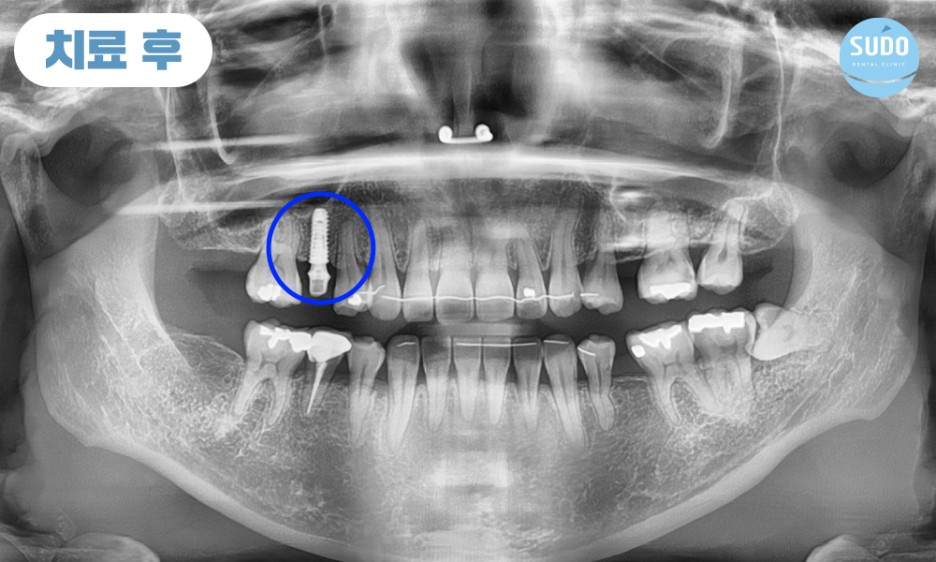

위 환자분은 30대 초반 여성분으로, 고등학생일 때 치료 받았던 금니가 빠져 저희 수도치과에 내원해 주셨습니다.

그 부분만을 확대하여 x-ray 사진 촬영해 본 결과 치아 뿌리 안쪽까지 심한 충치로 인해 발치 후 임플란트를 진행하셔야 하는 상태였습니다. 임플란트 경험이 없으셨던 환자분을 위해 수도치과 의료진들의 충분한 치료 설명을 통해 발치 후 부산영도임플란트 식립 계획을 수립하였습니다.

처음 내원하셨을 때는 외국 거주 중이셨고, 열흘 후에 출국 예정이셨습니다. 이에 따라 내원 당일에 발치 후 즉시 임플란트를 식립하셨고, 주변 치아의 이동을 예방하기 위해 유지 철사를 부착한 후 다시 출국하셨습니다.

임플란트를 식립한 후 11월에 다시 한국을 방문하셨는데, 시간이 제한적이어서 며칠밖에 계시지 못하는 상황이라 부산영도임플란트의 상태를 확인한 후 맞춤형 지대주와 임시치아를 제작하여 장착한 후 다시 출국하셨습니다.

외국에 거주 중이신 분이라 전체적인 치료 기간은 길어졌지만 큰 어려움 없이 마무리되었고, 5개월 정도 임시치아 상태로 편하게 사용하신 후 최근 다시 한국으로 돌아오셔서 최종 보철물까지 마무리할 수 있었습니다.